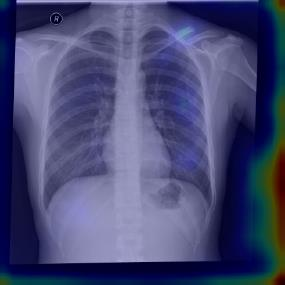

Chest X-ray (CXR) is the most typical diagnostic X-ray examination for screening various thoracic diseases. Automatically localizing lesions from CXR is promising for alleviating radiologists' reading burden. However, CXR datasets are often with massive image-level annotations and scarce lesion-level annotations, and more often, without annotations. Thus far, unifying different supervision granularities to develop thoracic disease detection algorithms has not been comprehensively addressed. In this paper, we present OXnet, the first deep omni-supervised thoracic disease detection network to our best knowledge that uses as much available supervision as possible for CXR diagnosis. We first introduce supervised learning via a one-stage detection model. Then, we inject a global classification head to the detection model and propose dual attention alignment to guide the global gradient to the local detection branch, which enables learning lesion detection from image-level annotations. We also impose intra-class compactness and inter-class separability with global prototype alignment to further enhance the global information learning. Moreover, we leverage a soft focal loss to distill the soft pseudo-labels of unlabeled data generated by a teacher model. Extensive experiments on a large-scale chest X-ray dataset show the proposed OXnet outperforms competitive methods with significant margins. Further, we investigate omni-supervision under various annotation granularities and corroborate OXnet is a promising choice to mitigate the plight of annotation shortage for medical image diagnosis.